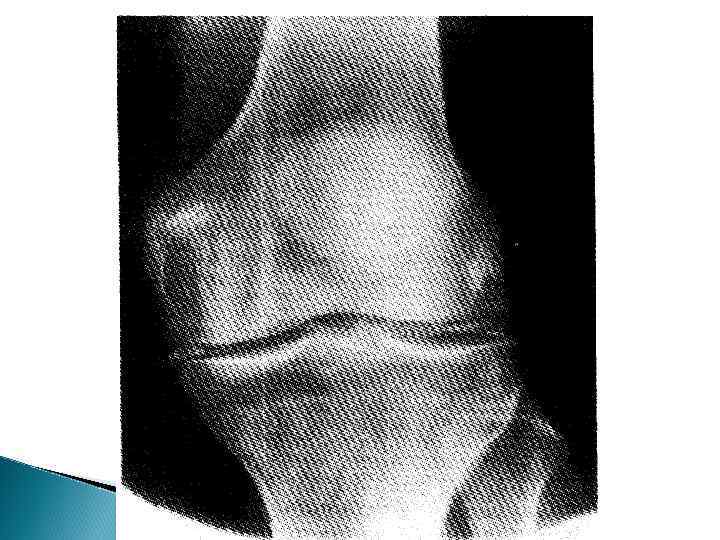

Пирофосфатная артропатия чаще у лиц старше 50 лет, с одинаковой частотой у мужчин и женщин артрит и/или артралгии, причем чаще в крупных суставах: коленных (70%), плечевых, голеностопных, лучезапястных рентгенологический феномен хондрокальциноза выявление кристаллов пирофосфата кальция в синовиальной жидкости

Клинические субтипы БДПФК (EULAR, 2010) 1. Лантонический или бессимптомный 2. Острый артрит (15 -18%) 3. Хронический артрит (10 -30%) 4. Остеоартроз с кристаллами ПФК (50%)